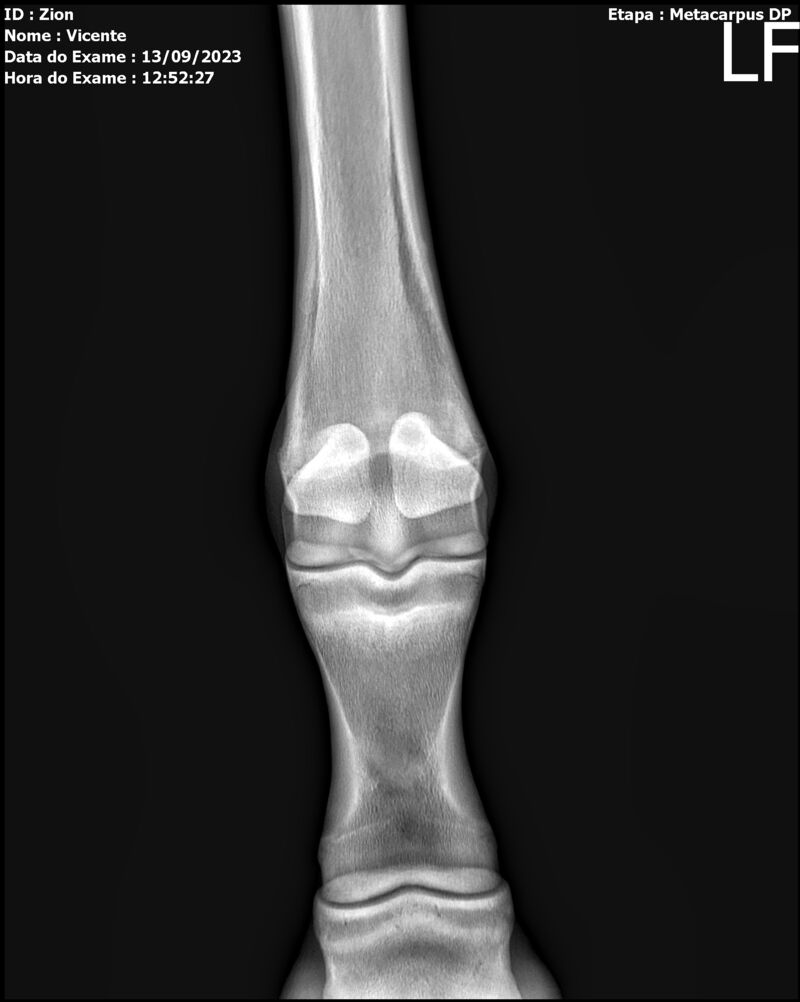

ZION ZC

Raça: BRASILEIRO DE HIPISMO

Sexo: MACHO - POTRO

Nascimento: 17/12/2022

Altura Aproximada: 1,51

Pel.: CASTANHO

Registro: EM AND

Vend.: VICENTE CONTE

Local : PORTO FELIZ/SP